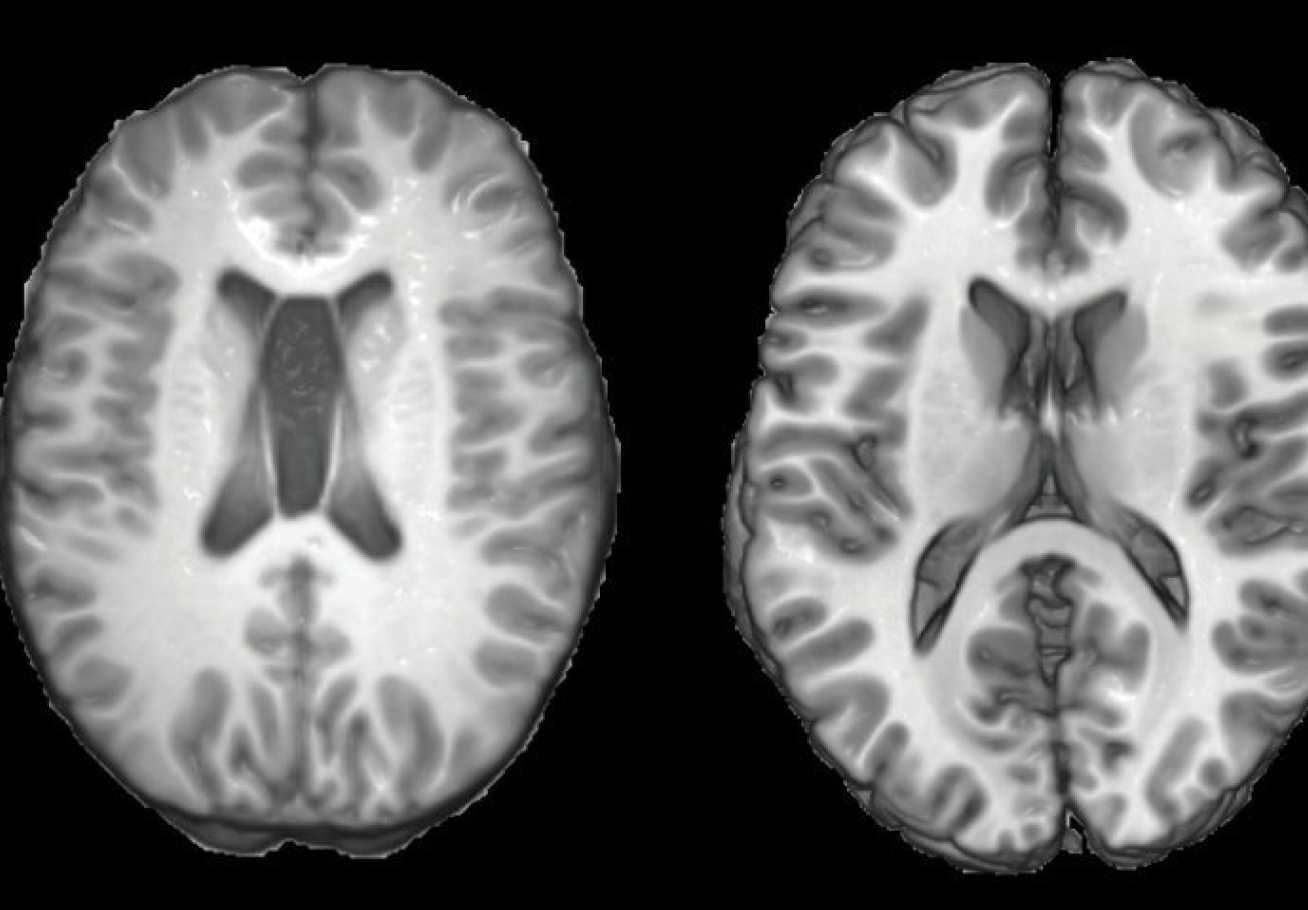

MRI scans from a traumatic brain injury patient (left) and a healthy person (right).

TBI is an injury to the brain caused by an external force such as in a car collision. The severity of the injury, ranging from mild to severe, determines the long-term effects on the patients. It is one of the most common causes of death and disability worldwide in people under 40 years old, but it’s often devastating effects are only just beginning to be recognised.

Professor Sharp and his team have developed a computer program that could predict a person’s age from their brain scan.

People who have suffered serious head injuries show changes in brain structure resembling those seen in older people. TBI patients were estimated to be around five years older on average than their real age. Head injuries are already known to increase the risk of age-related neurological conditions such as dementia later in life. The age prediction model may be useful as a screening tool to identify patients who are likely to develop problems and to target strategies that prevent or slow their decline.